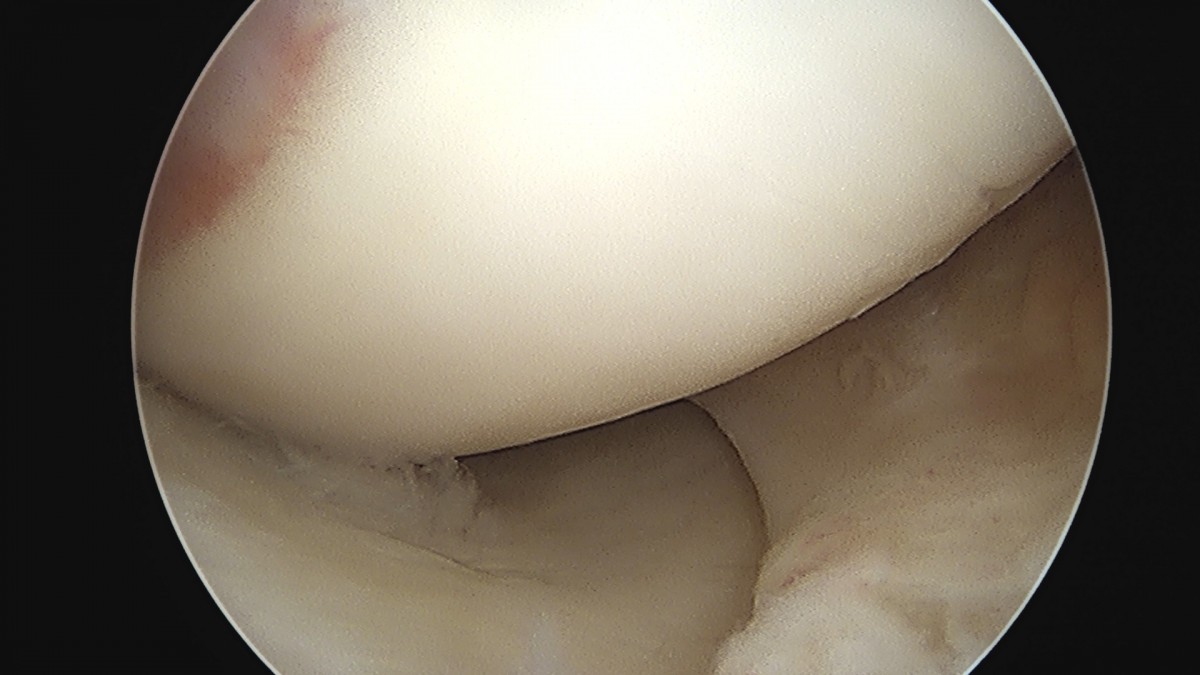

이재상원장님 무릎 전방십자인대 재건술 및 반월상 연골판 절제술 유해O 환자

dae765e4d9ac96aee867c9d6292d8784_1758007655_7733.jpg